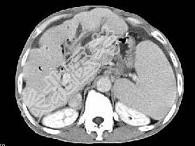

- 单项选择题根据所提供的图像,最可能的诊断是 ( )

A、肝囊肿

B、肝脓肿

C、肝胆管细胞癌伴肝硬化

D、肝细胞癌

E、以上都不是